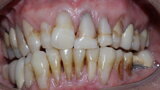

Figure 8 Right side in occlusion before treatment